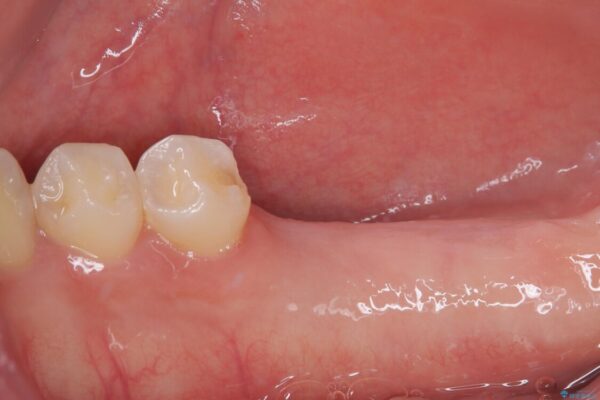

インプラント希望部位は右下第一大臼歯と第二大臼歯です。

しかし、噛み合わせの相手である右上の第二大臼歯が、長期間噛み合う歯がなかった影響で**挺出(歯が下に伸びてくる状態)してしまっており、このままではインプラントを埋入して被せもの(上部構造)を入れるためのスペースが不足している状態でした。

• 挺出歯を圧下してスペースを確保!目立たない部分矯正で下顎大臼歯にインプラント治療を実現 治療前画像